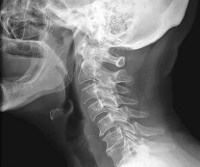

Для подтверждения диагноза назначают рентгенографию позвоночника, МРТ и КТ. Рентгенография шейного отдела информативна при наличии выраженных изменений в фасеточных суставах. КТ позвоночника более чувствительна и позволяет диагностировать спондилоартроз еще на начальных стадиях. На МРТ позвоночника видны сопутствующие изменения мягких тканей. Для оценки состояния мозгового кровообращения и исключения синдрома позвоночной артерии назначают допплерографию (УЗИ сосудов шеи и головы). При наличии неврологических нарушений больных направляют на консультацию к неврологу.